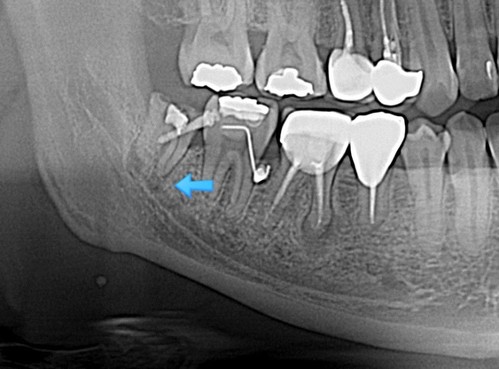

그리고 한 달이 더 흐른 후 x-ray를 확인하며 너무 행복했다.. 노력이 헛되지 않았으니

수술날짜를 잡고 나머지 뿌리도 깨끗하게 발치완료~